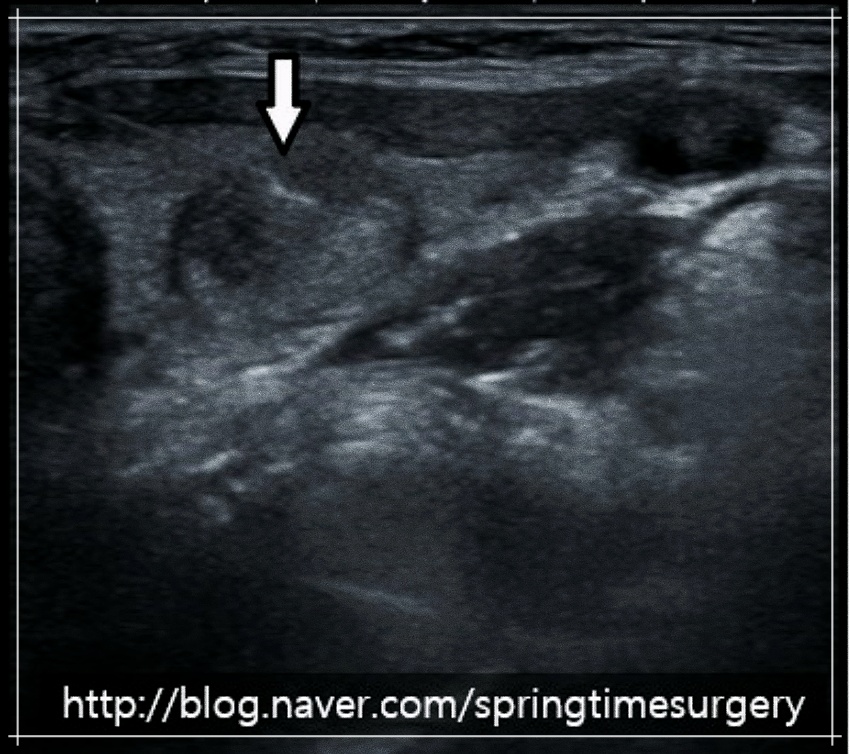

결절 부위에 작은 바늘을 삽입한 후 고주파열을 전달하여 결절을 구성하고 있는 조직을 괴사시키는 치료를 말합니다. 초음파로 결절을 보면서 바늘을 넣어 고주파 에너지를 전달하기 때문에 주변 정상 조직을 손상시키지 않는 것은 물론 시술 시간이 짧아 흉터나 부작용 발생률이 적다는 장점이 있습니다.